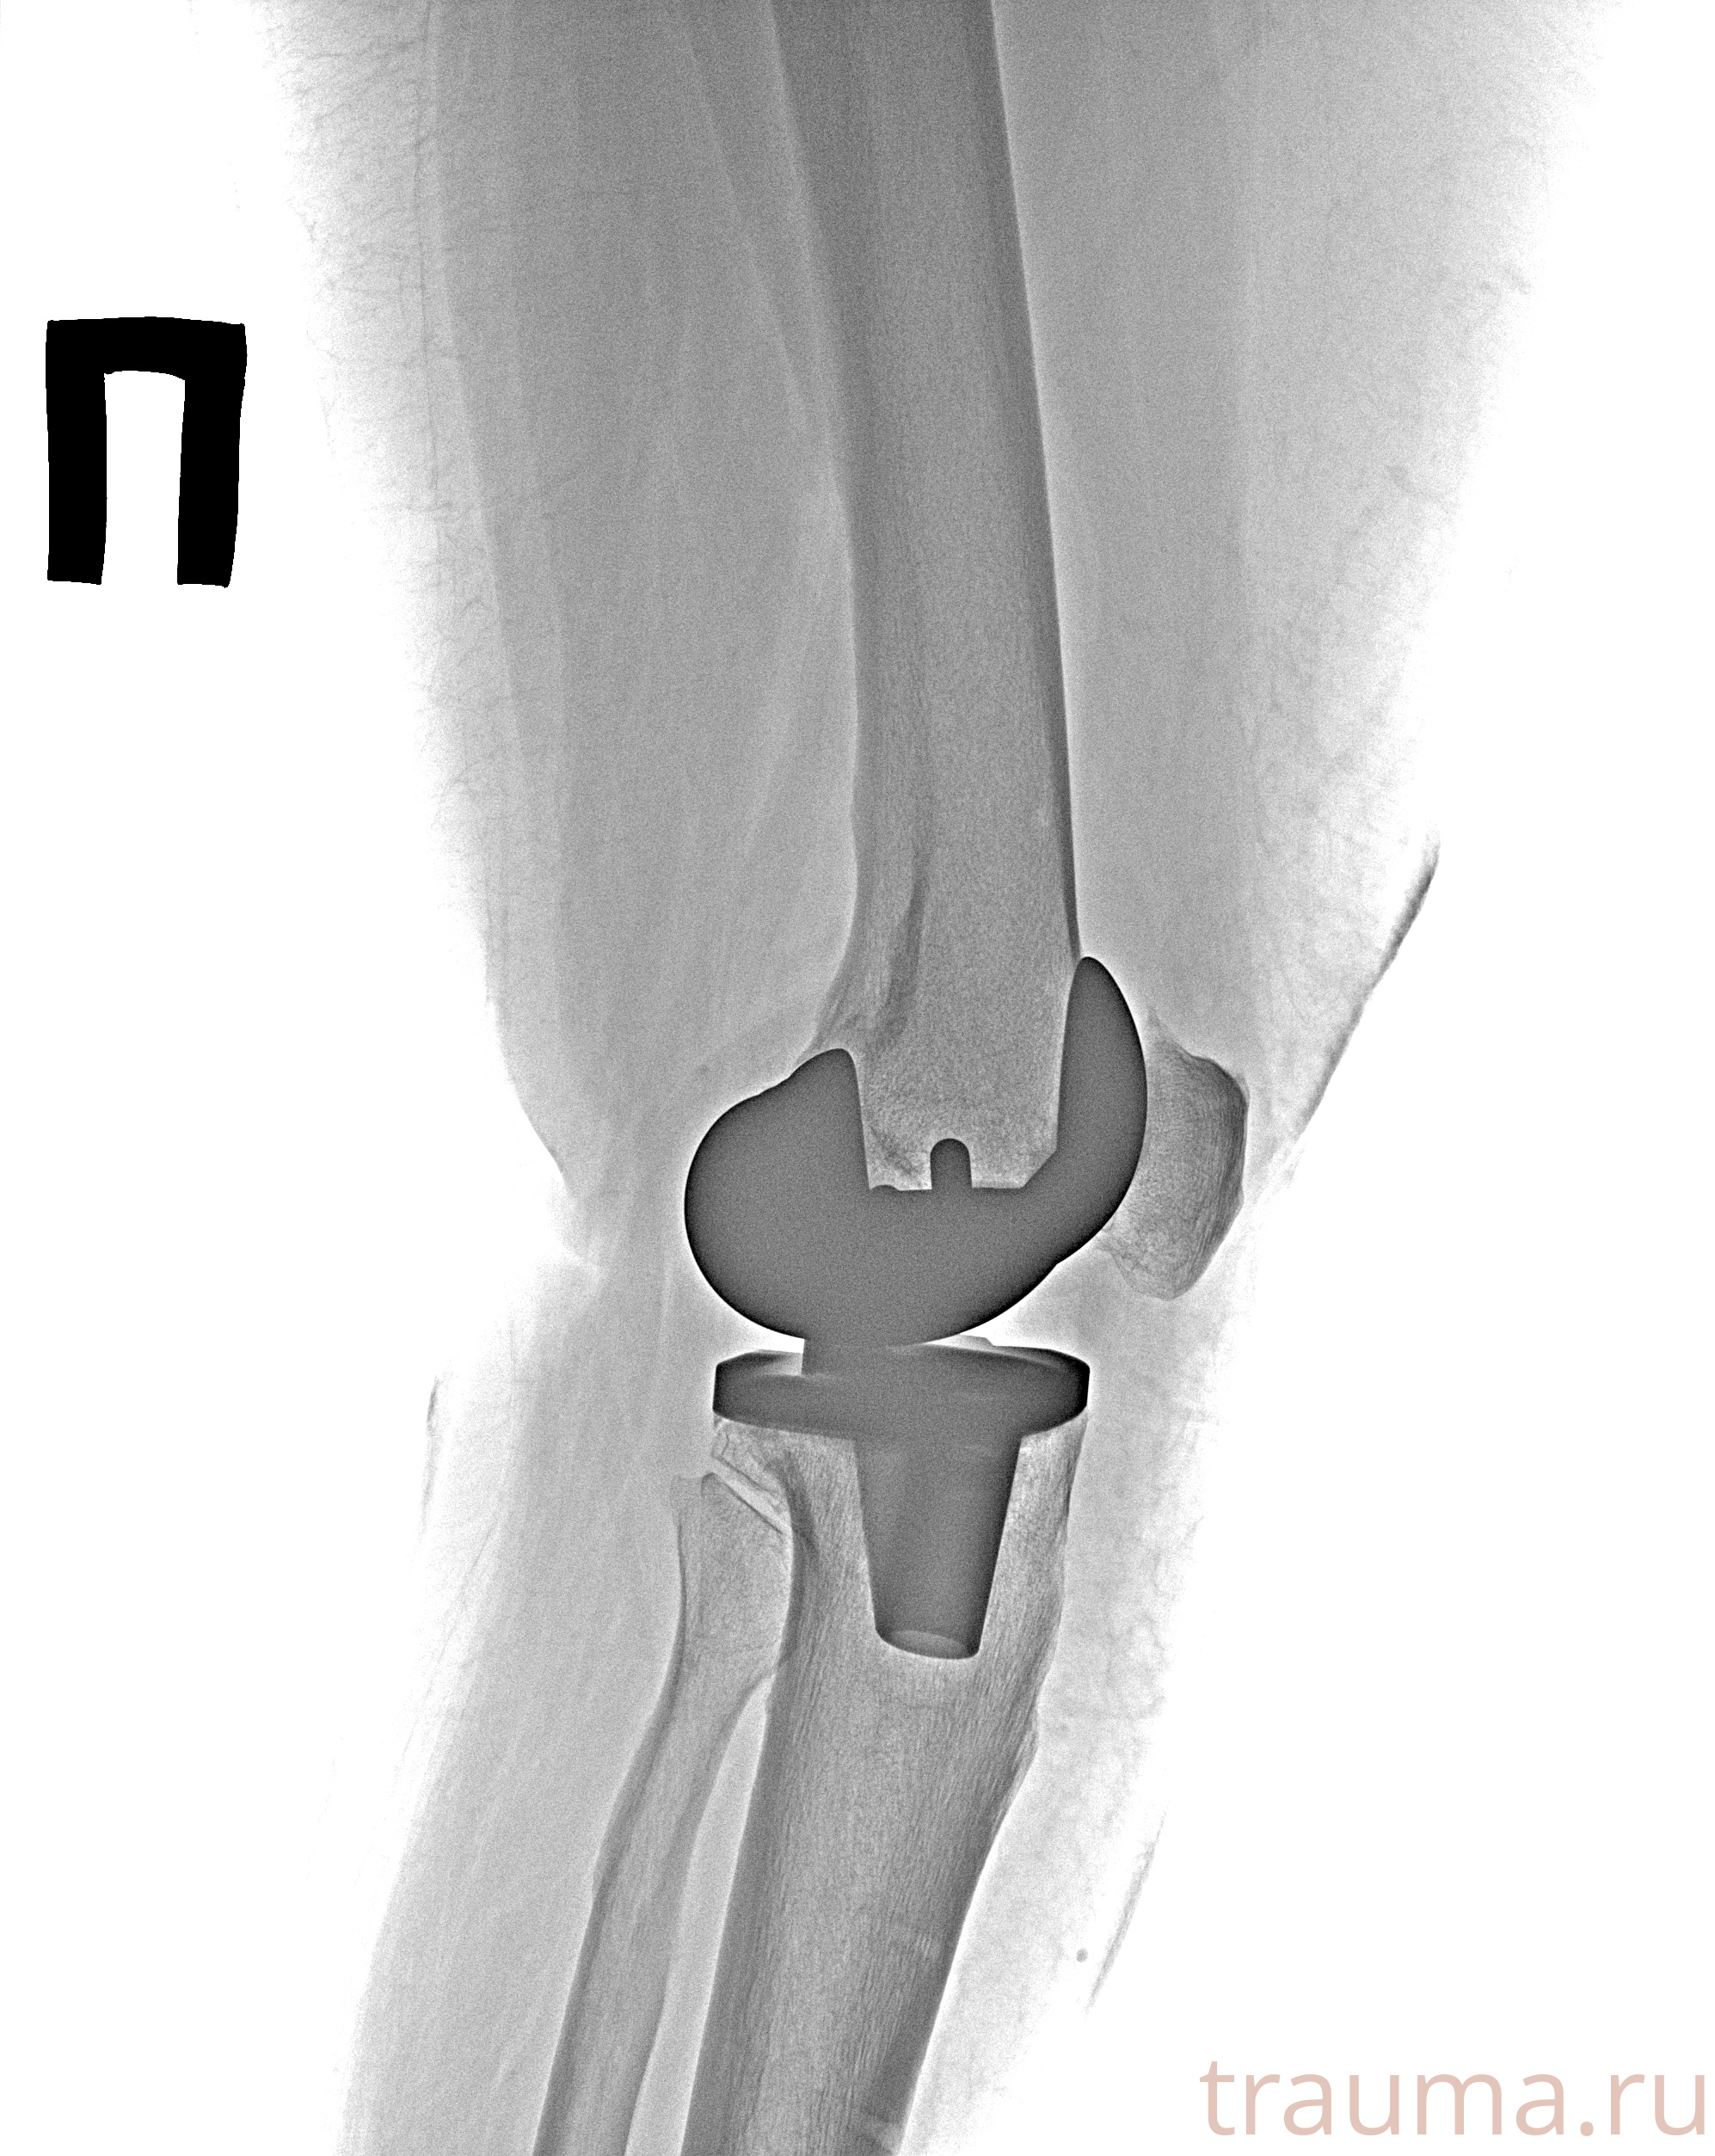

Рентгенограммы

Рентген на дому: по вашему адресу приезжает врач-рентгенолог, травматолог-ортопед с мобильным рентгеновским аппаратом, проводит диагностику травмы или заболевания, делает необходимые рентгенограммы, дает рекомендации по дальнейшему лечению. Получить качественные снимки в домашних условиях возможно благодаря уникальной методике, разработанной МосРентген Центром для института  Склифосовского